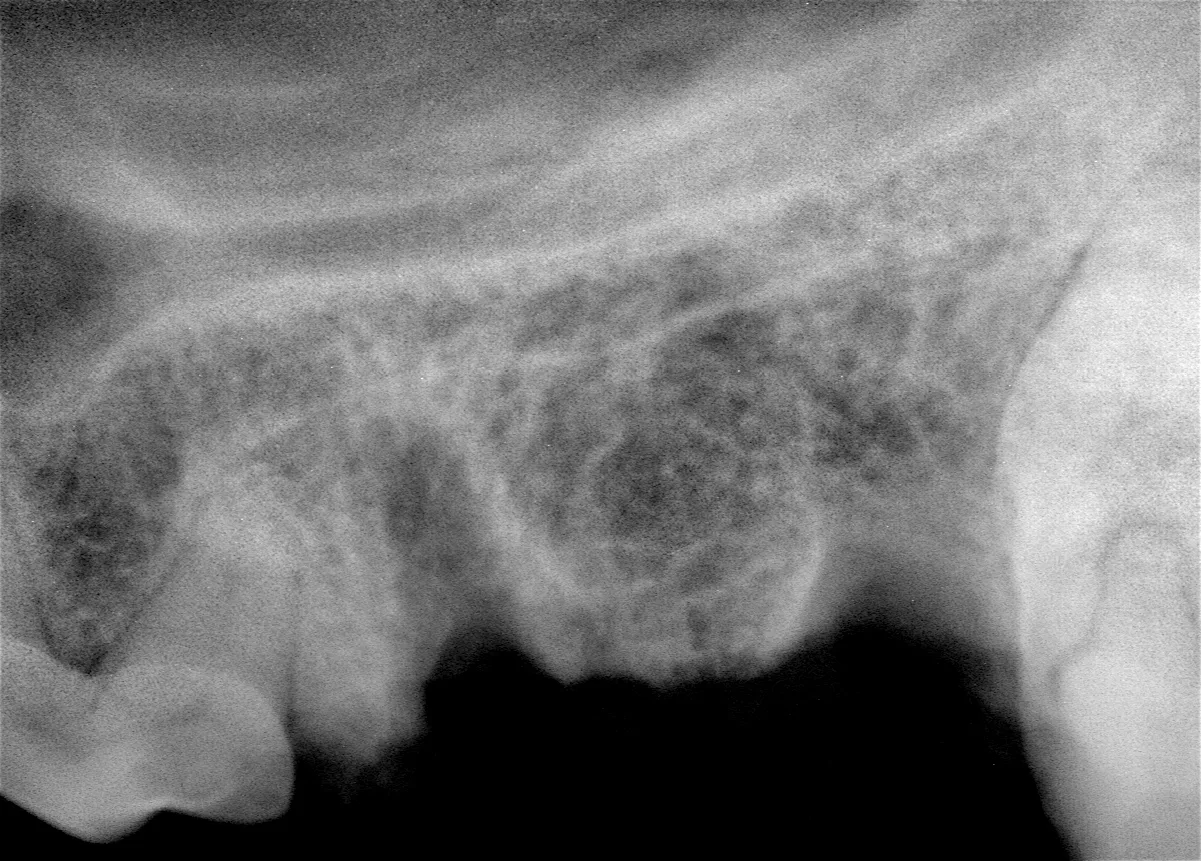

The patient is anesthetized, dental radiographs taken, tooth assessed, and multimodal pain management, including dental nerve block, instituted.

Preoperative radiograph of the maxillary left 4th premolar